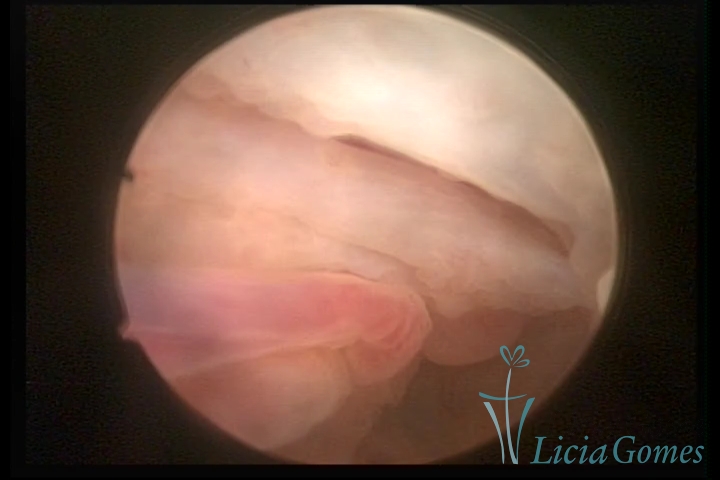

Terceira porção ou porção superior

Apresenta a mucosa com a superfície lisa e pouco vascularizada até a altura do orifício interno